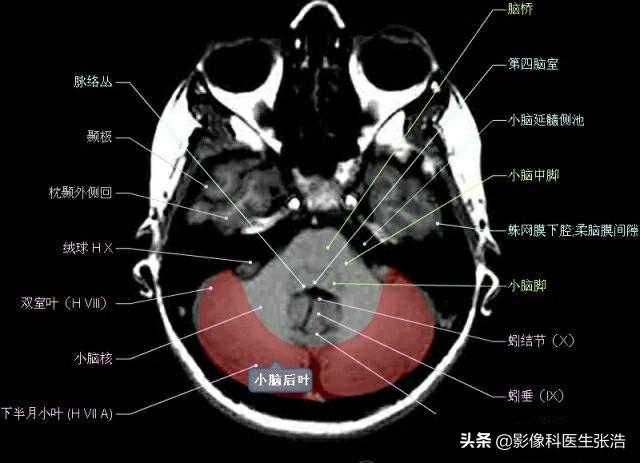

核磁共振(MRI)是一種利用磁場(chǎng)和射頻脈沖來生成身體內(nèi)部結(jié)構(gòu)的詳細(xì)圖像的非侵入性檢查技術(shù),頭部核磁共振主要用于檢查腦部疾病、神經(jīng)系統(tǒng)問題以及血管狀況等,這項(xiàng)檢查對(duì)于疾病的早期發(fā)現(xiàn)和治療具有非常重要的意義。